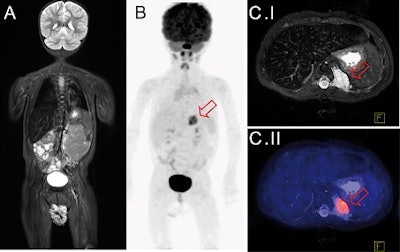

Whole-body FDG-PET/MRI exam of a 1-year-old girl with metastatic teratoma. Combined PET/MRI enables simultaneous acquisition of whole-body MRI (A) and PET (B) as well as local MRI (C.I). MRI shows a paravertebral metastasis (C.I, red arrow), which is metabolically active on FDG-PET (C.II, PET/MRI fusion image).

Whole-body FDG-PET/MRI exam of a 1-year-old girl with metastatic teratoma. Combined PET/MRI enables simultaneous acquisition of whole-body MRI (A) and PET (B) as well as local MRI (C.I). MRI shows a paravertebral metastasis (C.I, red arrow), which is metabolically active on FDG-PET (C.II, PET/MRI fusion image).The PET/CT results suggested an additional MRI scan for local staging and therapy planning for four patients, but the recommendation proved unnecessary except in one case.

"This additional examination [based on PET/CT] became unnecessary after PET/MRI, where local imaging was performed together with whole-body staging in one single examination," the authors wrote. "In one patient, the detection of a suspicious morphological MR correlate for focal tracer accumulation initiated close follow-up imaging and extended treatment."